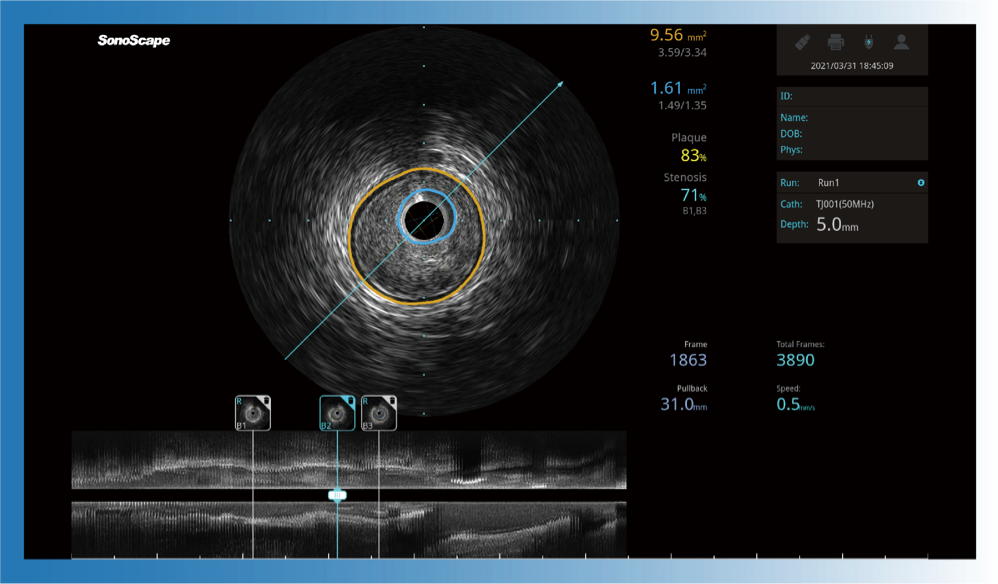

• 1xBET宽频IVUS图像

• 传统IVUS图像

对比传统IVUS导管成像,1xBET宽频IVUS图像的近场支架梁显影更细腻,远场中膜外血管仍清晰可辨,兼顾远中近,兼顾分辨力与穿透深度

一键智能描迹,自动测量斑块负荷、面积狭窄率等指标,准确率高于90%